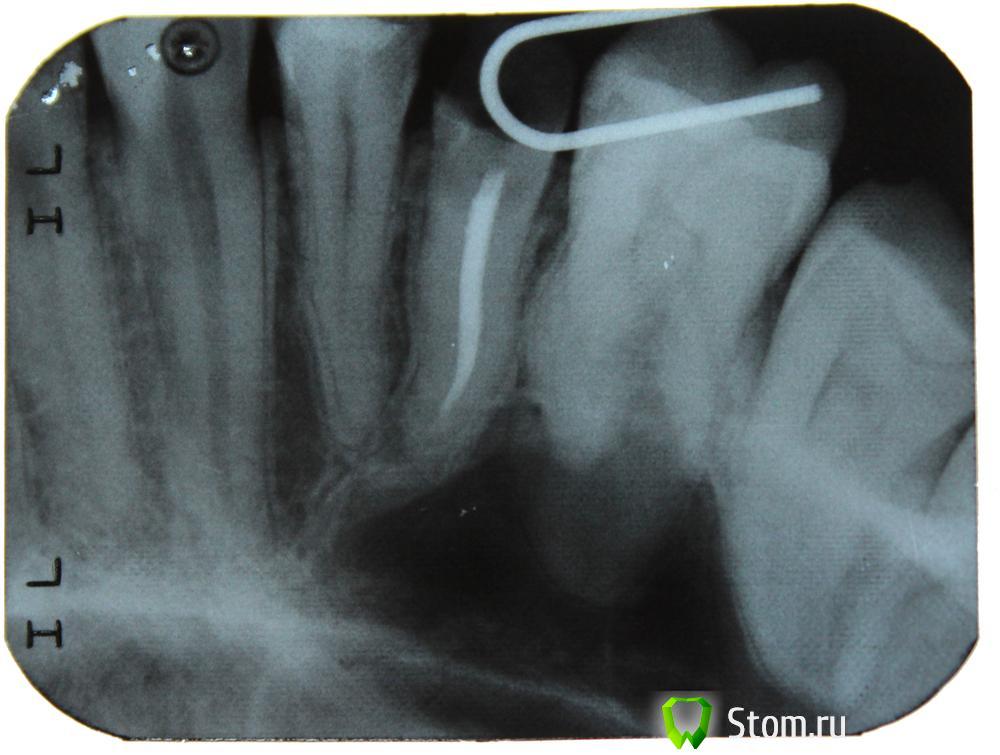

DsLog Опубликовано 31 января, 2012 Поделиться Опубликовано 31 января, 2012 Добрый день! Разрушены 2 зуба (5) верхней челюсти, врач клиники в которую обратился сказал что нужны снимки, принёс снимки, сказали что нужно удалять эти 2 зуба...удалять сказали в городской поликлиннике т.к. корень искревлён и они не смогут сами его удалить,.... после удаления предложили вариант: мост из металлокерамики со стачиванием двух соседних зубов и удалением из них нерва. Действую по принципу доверяй - но проверяй. Если зубы никак восстановить нельзя, то думаю что буду ставить импланты. Ссылка на комментарий

ger_berra Опубликовано 31 января, 2012 Поделиться Опубликовано 31 января, 2012 Удалять оба.На их место импланты.Не соглашайтесь на умышленное умертвление живых зубов!1-ый корень сгнил изнутри ниже уровня десны и вершины межальвеолярной перегородки.2-й высоты оставшихся твёрдых тканей недостаточно для изготовления ВКВ.Если только хирургическое удлинение.И то это будет компромисный вариант. Ссылка на комментарий